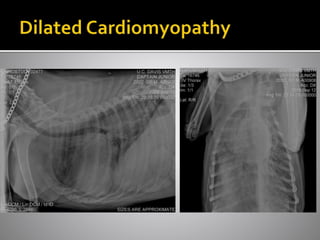

 Dilated cardiomyopathy

 Large breed dog – GSD, Boxer, Irish

Wolfhound, Doberman

 Large breed dogs

 Soft murmur can = severe

disease